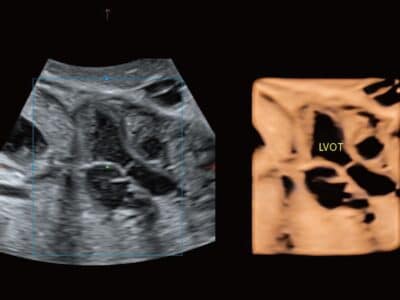

STIC

Zprůměrováním snímků v časové a prostorové dimenzi může STIC na přístroji P20 Elitte rekonstruovat obraz v různých rovinách pro komplexní vyšetření a vyhodnocení rychle se pohybujících srdečních struktur plodu z různých úhlů, což je užitečné zejména pro diagnostiku vrozených srdečních vad.